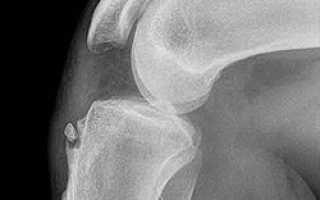

на фото изображена болезнь Осгуда-Шляттера